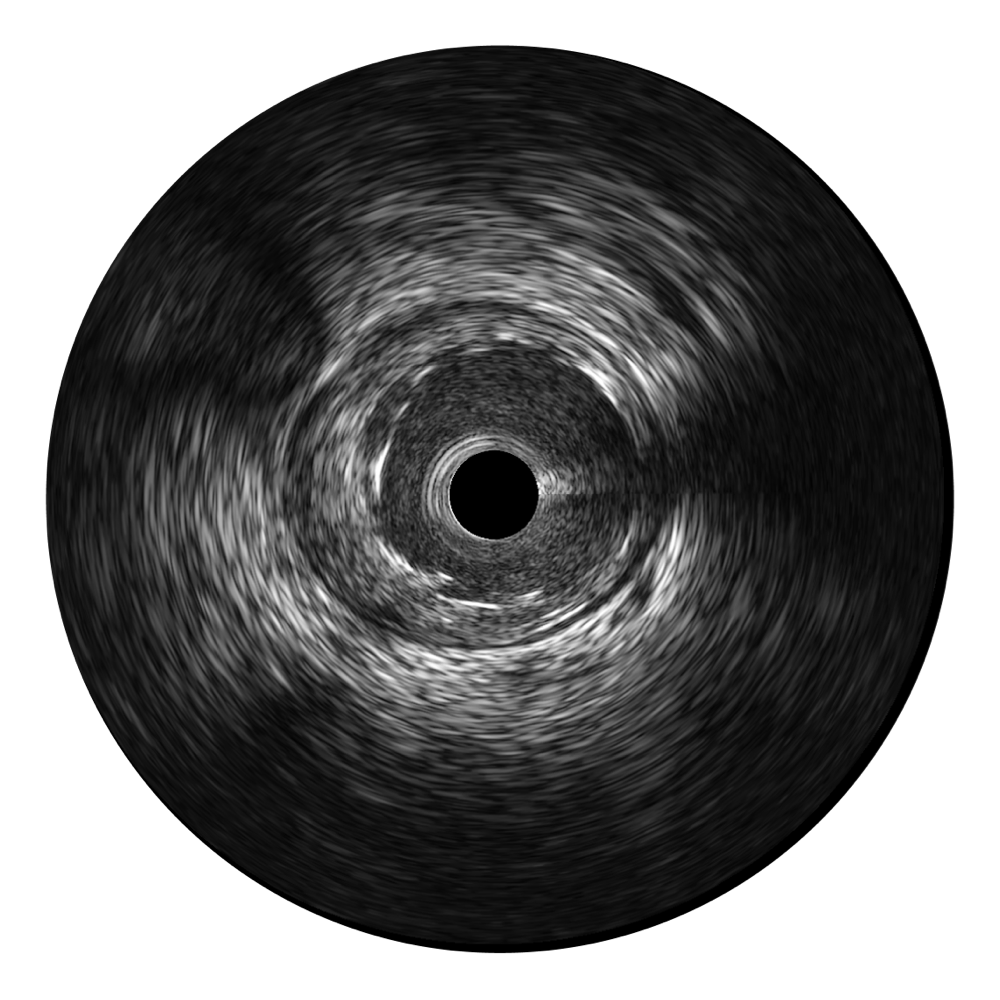

传统IVUS图像

对比传统IVUS导管成像,环球UG官网宽频IVUS图像的近场支架梁显影更细腻,远场中膜外血管仍清晰可辨,兼顾远中近,兼顾分辨力与穿透深度